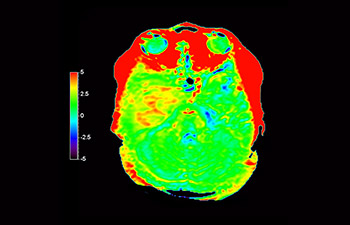

In a society where neurological disorders represent a heavy burden, Philips is committed to provide superb diagnostic clarity and treatment guidance for all patients. Today, although MR is the gold standard in neuro oncology imaging, its accuracy in tumor grading and treatment follow up assessment can be further improved. 3D APT (Amide Proton Transfer) is a unique, contrast-free, brain MR imaging method addressing the need for more confident diagnosis in neuro oncology. 3D APT uses the presence of endogenous cellular proteins, to produce an MR signal that directly correlates with cell proliferation, a marker of tumoral activity. 3D APT can support trained medical professionals in differentiating low grade from high grade gliomas and, in differentiating tumor progression from treatment effect1.